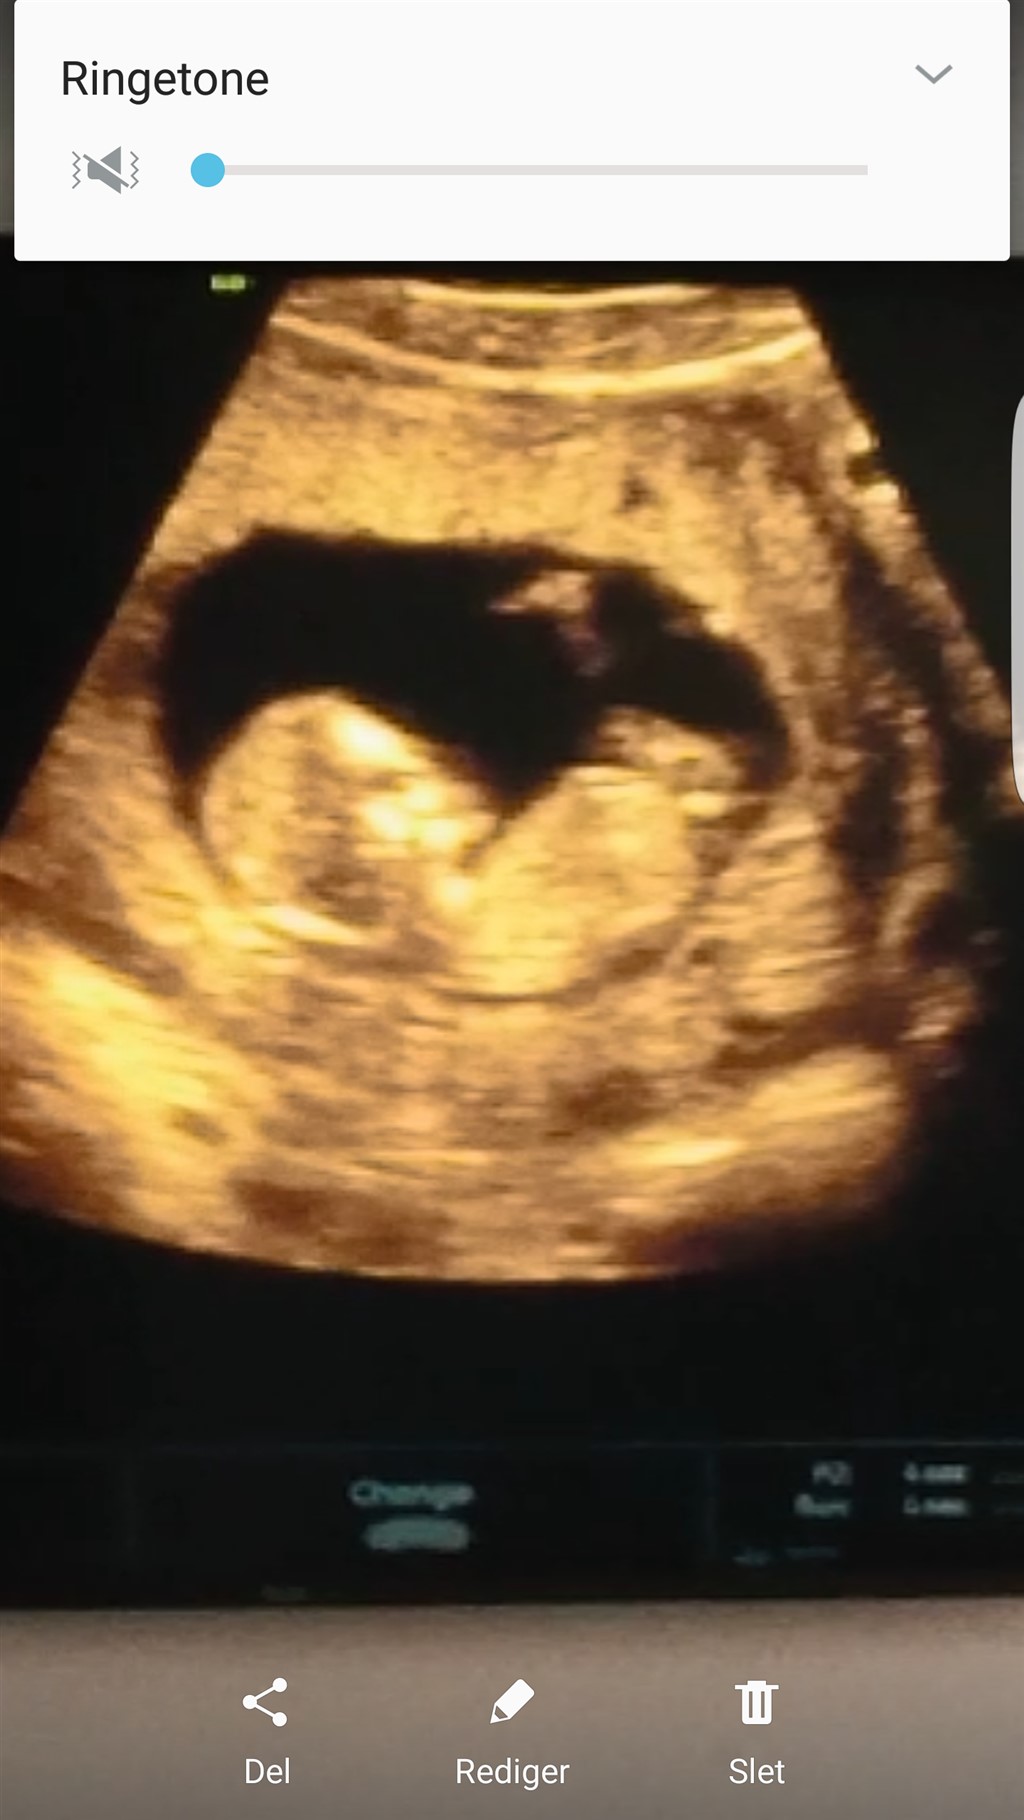

Hej alle. Hvad tror I denne lille skabning er?

Det er svært at se på det billede. Men et forsigtigt bud er en pige

Mit eget gæt er også en pige